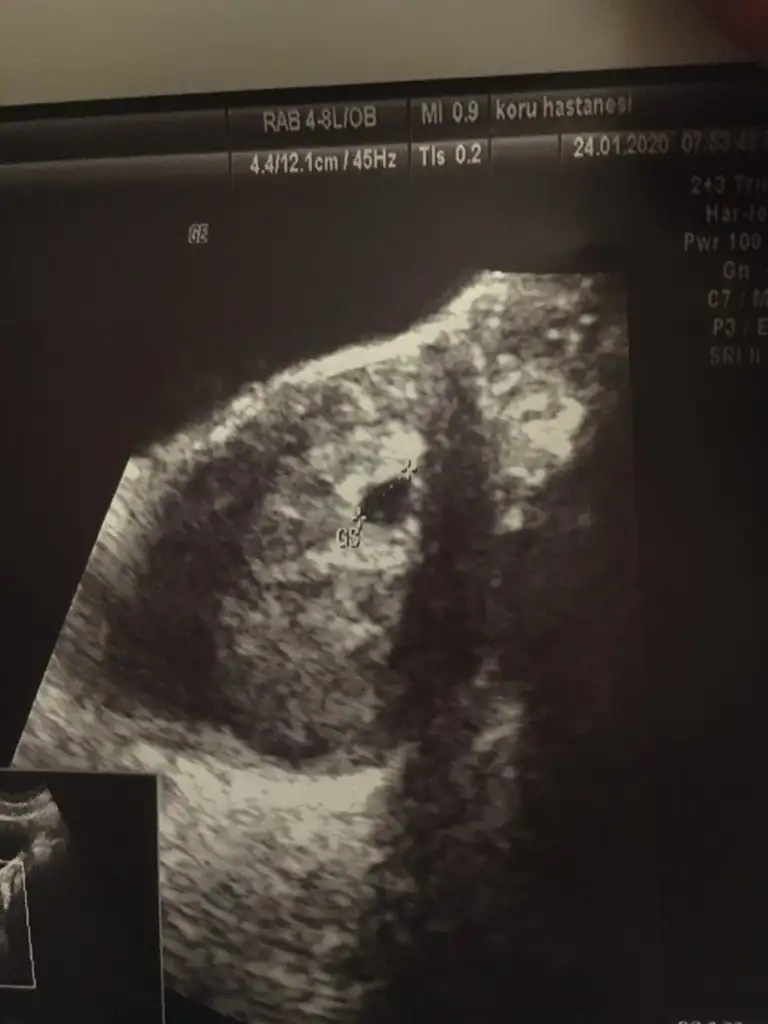

Şimdi Hastaneden geliyorum keseyi gördük 5 haftalık ama kanama alanı varmış düşük tehlikem var iğne yaptıDinlen bol bol dr igne verdimi

Yatarak geçiyo rahmine baskı uygulamaŞimdi Hastaneden geliyorum keseyi gördük 5 haftalık ama kanama alanı varmış düşük tehlikem var iğne yaptıyatıcakmışım hep